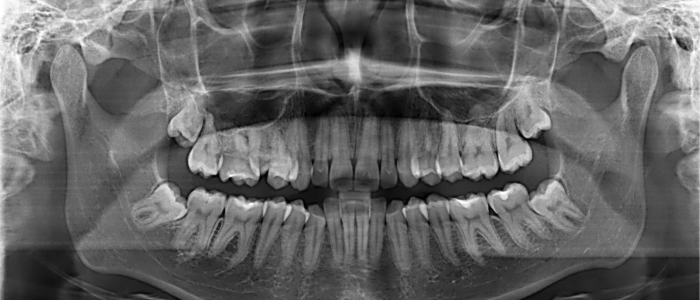

Radiografías Extraorales

Las radiografías extraorales se emplean cuando no es factible obtener información diagnóstica adecuada en las series de radiografías intraorales, es así que son utilizadas para observar un área grande de los maxilares y del cráneo en una sola radiografía. Los exámenes radiográficos extrabucales tienen el propósito de evaluar áreas grandes del cráneo, dientes impactados y patrones de erupción, crecimiento y desarrollo; examinar la extensión de lesiones grandes, traumatismos, articulación temporomandibular. Son de mucha utilidad principalmente en Ortodoncia y Cirugía Bucal.

Existen varias radiografías extraorales entre las cuales se tiene: